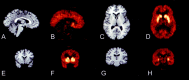

Studies in nonhuman primates documented that appropriate stimulation of dopamine (DA) D1 receptors in the dorsolateral prefrontal cortex (DLPFC) is critical for working memory processing. The defective ability of patients with schizophrenia at working memory tasks is a core feature of this illness. It has been postulated that this impairment relates to a deficiency in mesocortical DA function. In this study, D1 receptor availability was measured with positron emission tomography and the selective D1 receptor antagonist [11C]NNC 112 in 16 patients with schizophrenia (seven drug-naive and nine drug-free patients) and 16 matched healthy controls. [11C]NNC 112 binding potential (BP) was significantly elevated in the DLPFC of patients with schizophrenia (1.63 +/- 0.39 ml/gm) compared with control subjects (1.27 +/- 0.44 ml/gm; p = 0.02). In patients with schizophrenia, increased DLPFC [11C]NNC 112 BP was a strong predictor of poor performance at the n-back task, a test of working memory. These findings confirm that alteration of DLPFC D1 receptor transmission is involved in working memory deficits presented by patients with schizophrenia. Increased D1 receptor availability observed in patients with schizophrenia might represent a compensatory (but ineffective) upregulation secondary to sustained deficiency in mesocortical DA function.